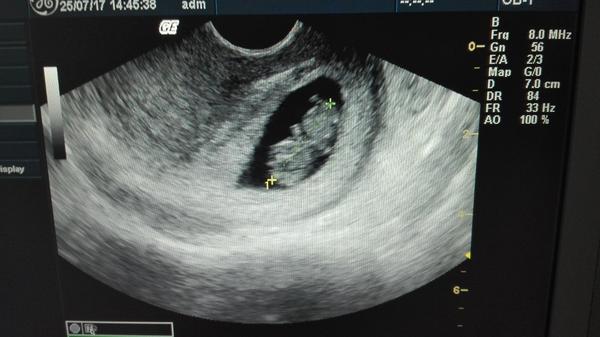

Ahojte kočky tak dnes som 32DC (16DPO) a teraz som už konečne pokojnejšia a začínam sa tešiť že čiaročka je silná....no kuknite